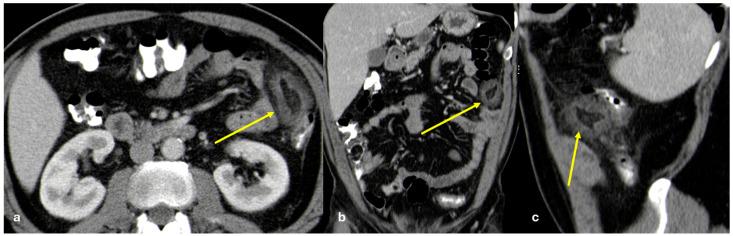

The peritoneum is a thin membrane that lines the abdominal cavity and covers the abdominal organs. It serves as a conduit for the spread of various pathological processes, including gas and fluid collections, inflammation, infections, and neoplastic conditions. Peritoneal carcinomatosis is the most common and well-known pathology involving the peritoneum, typically resulting from the dissemination of gastrointestinal and pelvic malignancies. However, numerous benign and malignant peritoneal diseases can mimic the imaging appearance of peritoneal carcinomatosis. The aim of this review is to revisit the anatomy of peritoneal compartments and elucidate the patterns of peritoneal disease spread. Emphasis is placed on identifying the distinctive imaging features of both neoplastic and non-neoplastic peritoneal diseases that differ from peritoneal carcinomatosis.

腹膜是一层薄的膜,它衬于腹腔内并覆盖腹部器官。它是各种病理过程扩散的通道,包括气体和液体聚集、炎症、感染及肿瘤性疾病。腹膜癌病是涉及腹膜的最常见且广为人知的病理情况,通常由胃肠道和盆腔恶性肿瘤的播散引起。然而,许多良性和恶性腹膜疾病可模仿腹膜癌病的影像学表现。本综述的目的是重新审视腹膜腔室的解剖结构并阐明腹膜疾病的扩散模式。重点在于识别与腹膜癌病不同的肿瘤性和非肿瘤性腹膜疾病的独特影像学特征。